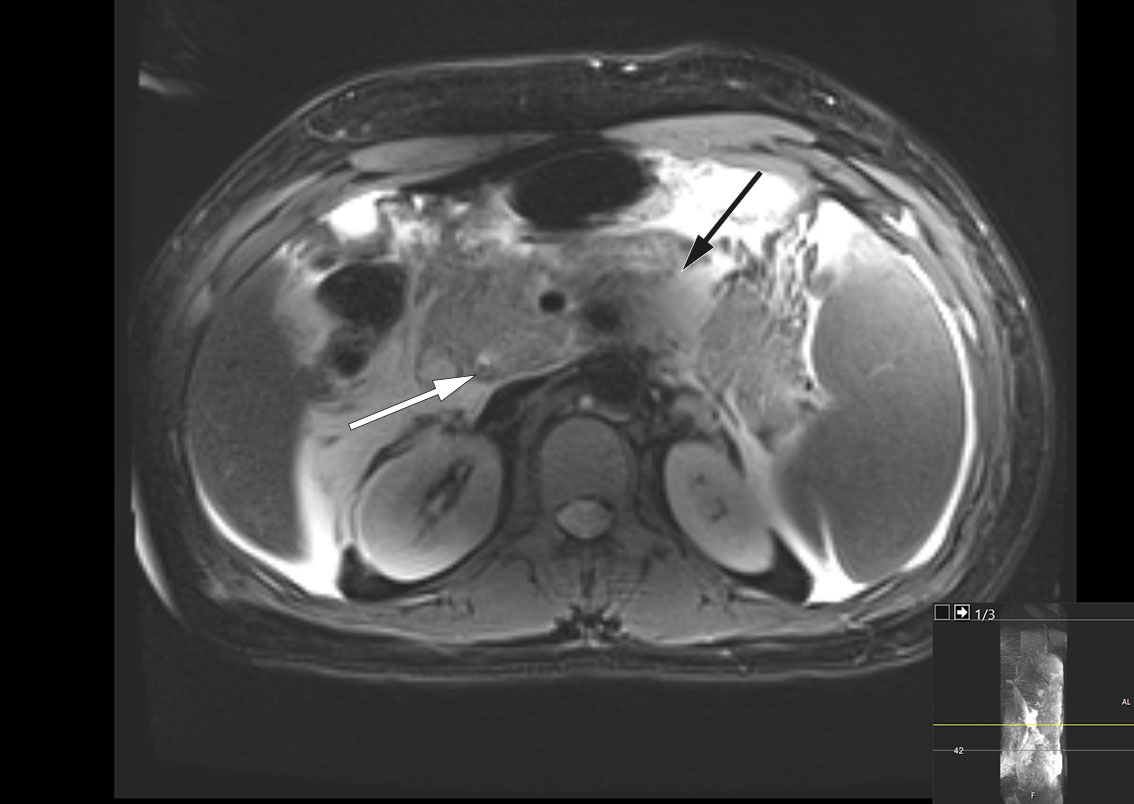

MRCP was performed the same day and revealed peripancreatic fluid collections and a 4 mm stone in the distal common bile duct (Figure 1). There were also pronounced signs of pancreatitis with surrounding oedema and fluid collections in the upper abdomen. By day 3 after admission, the patient's condition had worsened, and he was experiencing nausea and increased pain. Blood tests showed persistent leukocytosis at 45.6 × 109/L. His CRP level had increased to 261 mg/L, and his bilirubin level had increased further to 290 μmol/L. Broad-spectrum intravenous antibiotics were initiated in the form of piperacillin/tazobactam 4 g/0.5 g three times daily due to suspicion of concurrent infection in the biliary tract. The patient was also referred for endoscopic retrograde cholangiography (ERC), which was performed without complications, with papillotomy followed by removal of two black stones from the distal common bile duct. Cholangiography revealed the gallbladder to be full of stones. Later that day, the patient's bilirubin level was found to have decreased to 139 μmol/L.